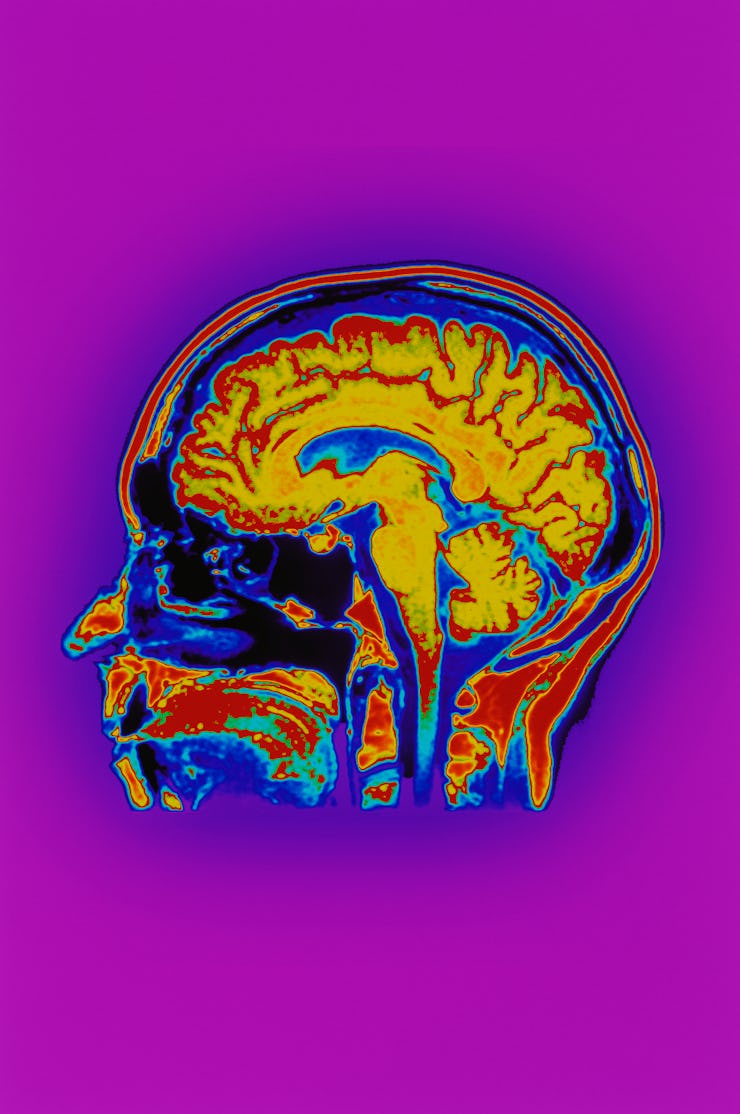

Ketamine is an N-methyl-D-aspartate receptor antagonist, which means it tamps down the activity of these receptors. This inhibition is thought to explain why it works as an anesthetic but over the years scientists have found ketamine causes a wide range of different molecular effects. Research suggests ketamine can prompt neuronal growth while increasing levels of glutamate in the brain. This effect is why ketamine can cause one to be in a dissociative state — it is also why it’s used in medicine and popular as a party drug.